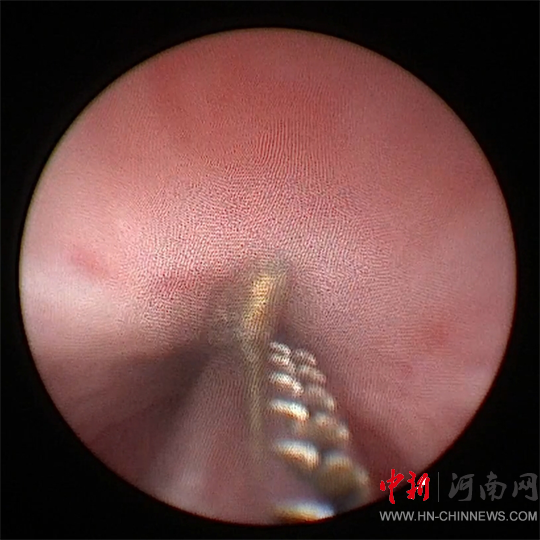

采用小兒輸尿管鏡

和異物鉗進(jìn)行手術(shù)

徐海亮在精細(xì)操作下

謹(jǐn)慎調(diào)整異物角度

一點(diǎn)一點(diǎn)往外取

歷時(shí)20分鐘

順利將鋼針取出